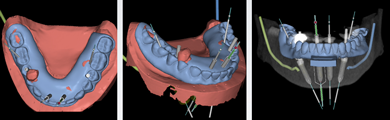

Intra- and extraoral photographs, intraoral scans, and analog impressions were taken and a CBCT was acquired. A digital smile design was accomplished and records sent to the laboratory (Figure 27). The digital records and analog models were scanned and imported into the digital denture scanning software that was used to plan the denture. The denture plan was then imported into the implant planning software (Nobel DTX Studio, Nobel Biocare; alternatively: X-Guide, X-Nav Technologies; Implant Studio, 3Shape) to create the plan for the implants (Figure 28). Next, the plan was imported into the navigation software system of the navigation unit, and the practitioner was able to begin planning bone reduction and screw positions.

Fig 15. The case was planned using navigation planning software in this same patient.

Fig 16. Virtual design of the provisional prosthesis.

Fig 17. Views of the milled PMMA screw-retained provisional restoration. Note the screw access holes in the incisor edges (left panel). (Images courtesy of Dr. Kim Knoll.)

Fig 27. Digital smile design, intraoral view.

Fig 28. Views of virtual digital denture used to plan implant position.